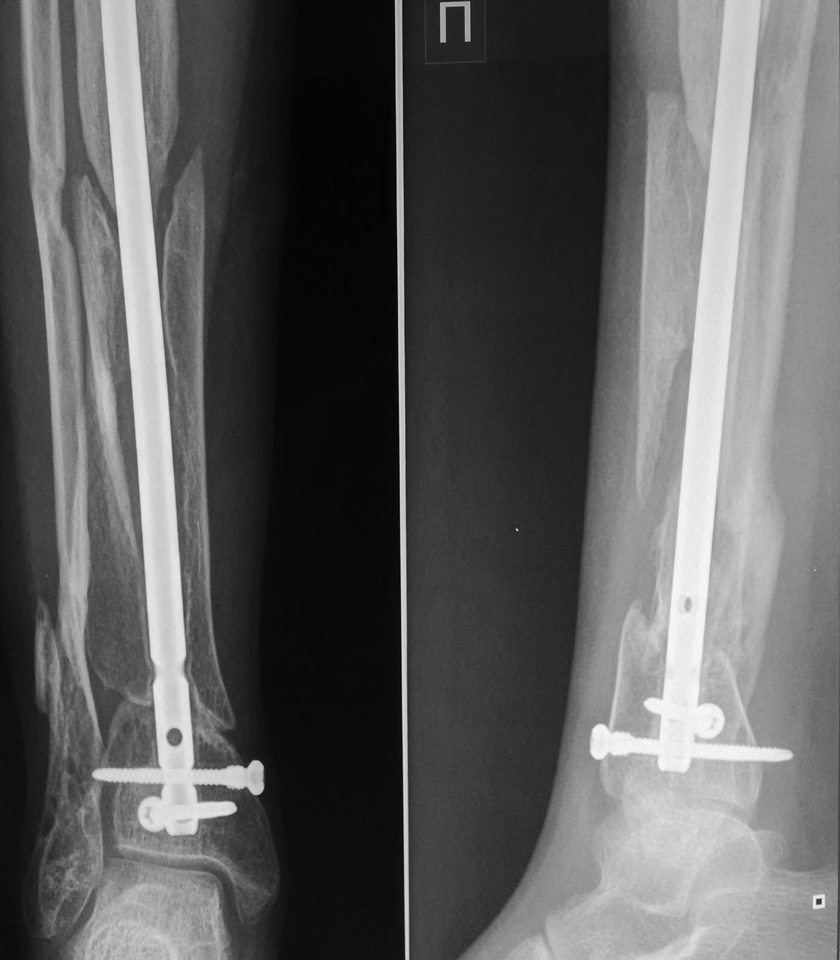

Женщина, 24 г. В июне прошлого года закрытый интрамедуллярный остеосинтез tibia (за 6 нед. до этого - открытый перелом голени после мотоаварии). На данный момент - клиника несращения. Проявлений инфекции нет. Снимки в приложении.

При первом рассмотрении представленной рентгенограммы сложилось впечатление о аваскулярном некрозе. Остеопороз прогрессирует. Биология нарушена. Есть желание проконсультировать у сосудистого хирурга, выполнить ангиографию.

Вопрос можно решить после изучения истинной топографии, особенно свободных фрагментов. КТ срезы или дополнительные косые снимки точно

укажут состояние разделенных друг от друга фрагментов в центре, а также атрофические регионы на различных уровнях.

Представленный случай очень интересен с точки зрения выбранной тактики лечения, её хирургической реализации. Без детального анализа этого подходить к выбору метода лечения очень рискованно. Сейчас необходимо понять: Что произошло, и тогда станет понятно что делать? Очень интересно увидеть рентгенограммы до выполненного остеосинтеза. По имеющимся можно предположить, что выбранный стержень оказался неадекватным диаметру костномозговой полости (она на этом уровне имеет овоидную передне-заднюю форму) и поэтому стал клином который разъединил отломки вдоль оси и стал причиной диастазов в разных плоскостях. Это о механике. Биология: диастазы очень быстро заполнились рубцовой тканью. Очень стабильный остеосинтез не способствовал формированию хотя бы несколько избыточной костной мозоли. В результате атрофический многоплоскостной псевдоартроз.

Дистальный отломок, такого размера - никогда не фиксируется двумя винтами. Нестабильность - режет глаза.